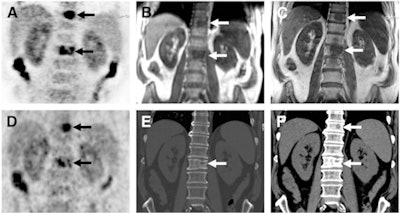

There were 98 conspicuous lesions (90 malignant, eight benign) in 33 of the 199 patients, according to the authors. All 98 lesions were identified on PET/CT (set A) and on the T1-weighted TSE sequence for PET/MRI (set C). The T1-weighted VIBE Dixon sequence (set B) missed one PET-negative malignant lesion in the ribs.

In pinpointing the location of the lesions, T1-weighted TSE (mean rating, 2.84 ± 0.42) performed significantly better than both CT (mean rating, 2.57 ± 0.54) and T1-weighted VIBE Dixon (mean rating, 2.57 ± 0.54).

Of the 98 lesions, 85 (87%) showed abnormally increased uptake on PET. Visual lesion conspicuity on PET was similar for both hybrid modalities, with a mean 2.82 ± 0.45 for the PET dataset from PET/CT and 2.75 ± 0.51 for the PET results with PET/MRI.

As for characterizing the lesions, the researchers found no significant differences between the three image sets. Of the 90 malignant lesions, 85 were correctly classified in set A, 84 in set B, and 86 in set C.

In addition, six PET-negative lesions were correctly classified as malignant bone lesions in the PET/CT and T1-weighted TSE images. Of those lesions, one was completely missed by the T1-weighted VIBE Dixon sequence in PET/MRI, but it was correctly recognized in the other two sets as malignant.